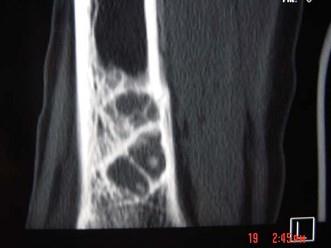

问题 男,30岁,感右小腿下段稍肿,其他无特殊,请结合所提供的图像,选择最佳选项 ( )

选项 A、良性骨肿瘤 B、纤维性骨皮质缺损 C、非骨化性骨纤维瘤 D、骨囊肿 E、骨结核

答案 C